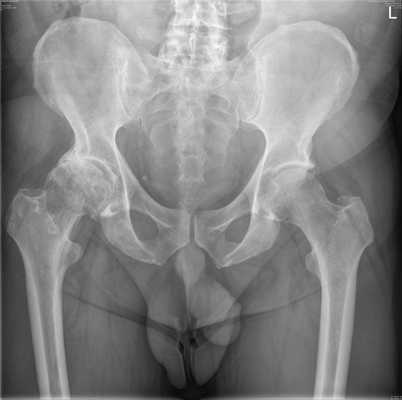

Диагностику асептического некроза костно-суставных структур осуществляют врачи-ортопеды. Раньше основным методом было рентгенологическое исследование, не позволяющее обнаруживать ранние патологические изменения. В настоящее время наряду с традиционной рентгенографией при постановке диагноза применяются современные методики, чувствительность которых на ранней стадии достигает 90-100%. План обследования включает следующие методы визуализации:

- Рентгенография тазобедренного сустава. Для повышения информативности используются специальные укладки по Лаунштейну. Вначале на снимках просматриваются участки со сниженной плотностью под субхондральной костью, придающие поверхностным частям головки вид «яичной скорлупы». Затем становится видна деформация головки и некротический очаг в виде плотной тени, окруженной более светлым ободком. В исходе визуализируются изменения, характерные для деформирующего артроза.